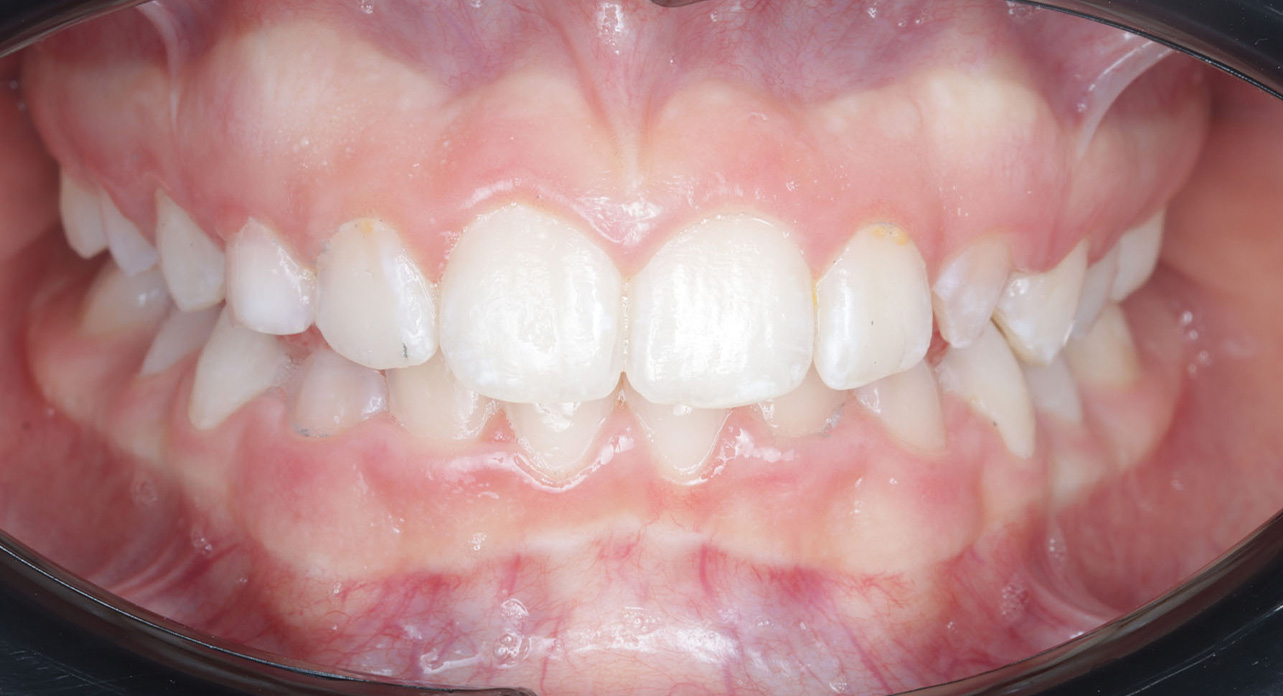

Case report of a 9-year-old female patient in the intermediate phase of mixed dentition. The patient presents with moderate upper and lower crowding, narrow arches, Class II molar relationship on the right side, premature loss of tooth 83, deviation of the lower midline to the right, deep bite, and a crossbite on the right side affecting only the deciduous dentition.

The goal of the treatment was to achieve transverse development of both arches, proclination of upper and lower incisors to correct the deep bite, and to create space for the blocked tooth.